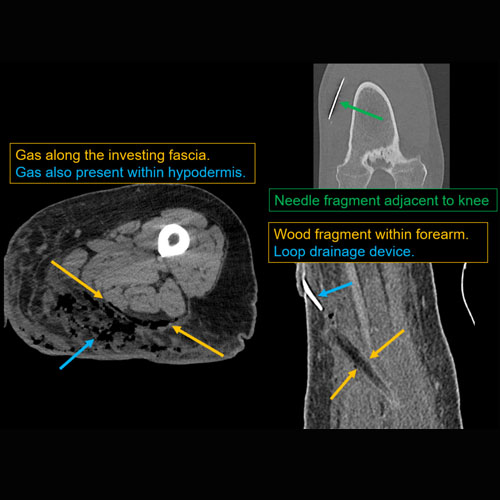

Right hand cellulitis.Exam

Findings

There is gas or foreign body. |

Yes | NA |

Soft tissue edema about the elbow, compatible with cellulitis.